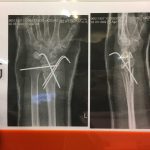

جراح و متخصص استخوان و مفاصل زانو و لگن ( ارتوپد )

برد تروماتولوژی

– شکستگی و در رفتگی